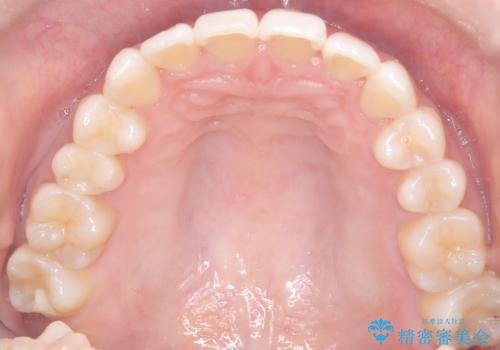

インビザラインモデレートによる前歯の叢生改善|IPR最小限で自然な歯並びへ

診査の結果、中等度の叢生であったため、インビザラインモデレートでの対応が可能と判断しました。

歯へのダメージを抑えるため、IPR(歯間削合)は必要最小限にとどめる方針としました。

前歯の叢生は解消され、自然で調和の取れた歯並びが得られました。

「歯をほとんど削らずにきれいになった」と、患者様にもご満足いただけました。